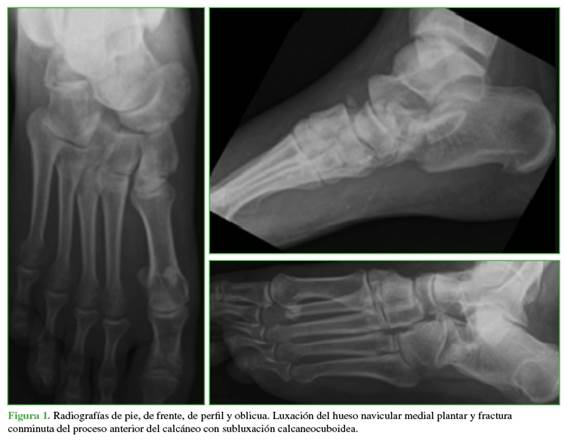

Se tomaron radiografías de pie, de frente, de perfil y oblicua sin carga (Figura 1) y se realizó una tomografía computarizada (Figura 2). Se observó una luxación del hueso navicular asociada a una fractura conminuta del proceso anterior del calcáneo y el cuboides con subluxación calcaneocuboidea.